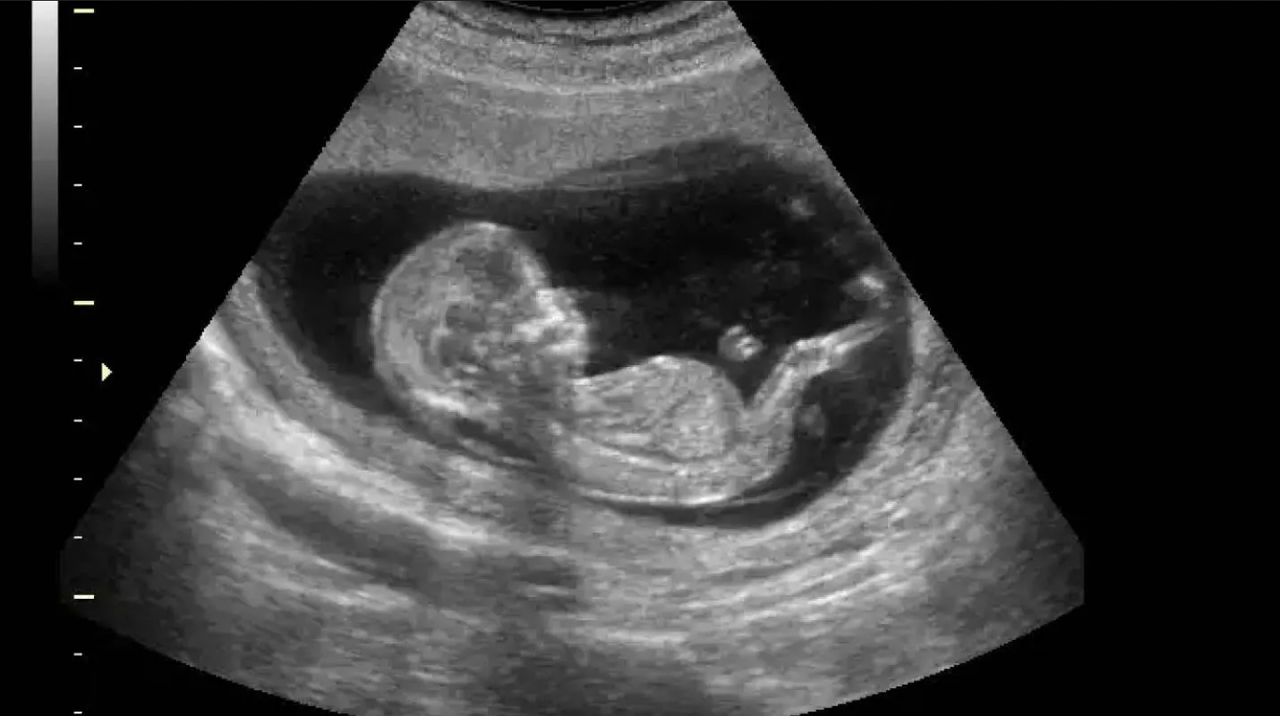

La misma que se publicó el dÃa miércoles en el Diario Oficial del municipio, busca ‘orientar y esclarecer a las gestantes los riesgos del procedimiento abortivo’, y esto incluye imágenes del desarrollo del feto semana a semana.